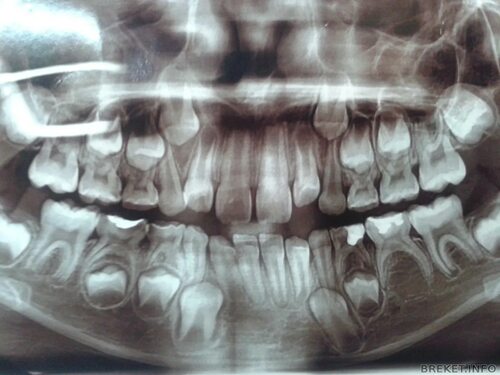

На изображениях вы увидите пятые зубы с разными степенями прорезывания, формами корней и положением в челюсти. Многие из этих фотографий были сделаны во время хирургического удаления пятых зубов, что дает нам возможность рассмотреть эту зубную структуру в деталях.

Уникальные фотографии пятого зуба помогут вам лучше понять анатомию и особенности этой зубной структуры. Вы сможете узнать, как пятый зуб выглядит внутри рта, и оценить его форму и размеры. Кроме того, некоторые фотографии позволят вам увидеть как проходит процесс удаления пятого зуба.